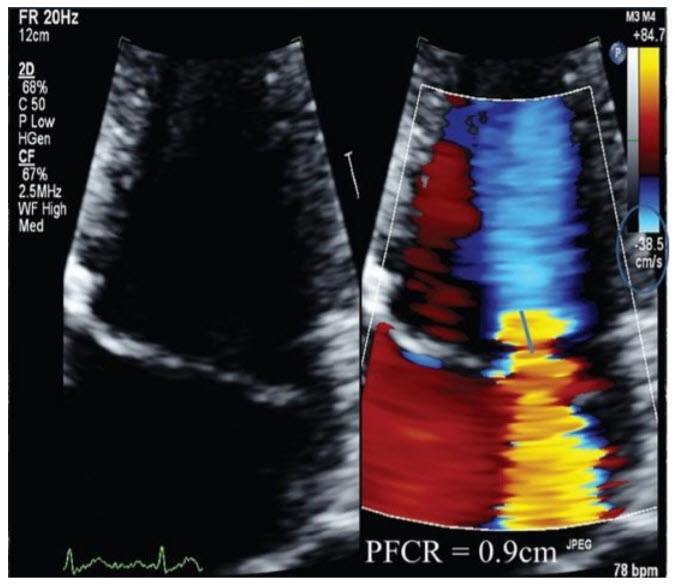

A 46-year-old woman with chronic obstructive pulmonary disease is referred by her pulmonologist for evaluation of a murmur and concern that her symptoms of shortness of breath with moderate exertion may be related to severe MR diagnosed on an outside echocardiogram. On examination, her body mass index is 19 kg/m2 , BP is 130/75 mmHg, and her heart rate is 75 bpm and regular. Her apex beat is nondisplaced. On auscultation, S1 and S2 are normal; there is a midsystolic click with a grade IV/VI late systolic murmur heard best at the apex. An echocardiogram is performed (Fig. below).

Assuming an aliasing velocity of 40 cm/s and an MR Vmax of 5 m/s, based on the PFCR seen here, what is the estimated effective regurgitant orifice area (EROA)?

0.4 cm2 . The EROA based on the assumptions above is 0.4 cm2 consistent with severe MR. The EROA is calculated using the abbreviated proximal isovelocity surface area (PISA) method as r 2 /2 (r = radius of the PFCR). In this case, the radius is 0.9 cm; therefore, the EROA can be estimated as 0.4 cm2.